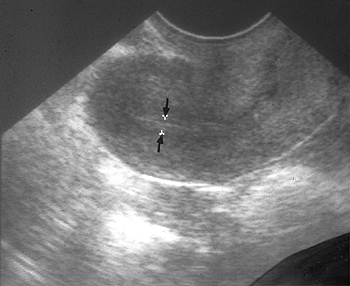

Endometrial thickness is significantly associated with fertility treatment outcome. However there is no reliable endometrium thickness by which receptive state of endometrium can be identified. The aim was to assess the relationships between endometrial thickness and IUI outcome.

In a retrospective study, the relationship between endometrial thickness and pregnancy rate has studied in 480 IUI cycles. Cycle parameters in pregnant and non-pregnant patients were compared. Endometrial thickness was measured by transvaginal ultrasound on the day of hCG administration. We examined the question of whether IUI is optimized by endometrial thickness. The patients were divided into four subgroups according to endometrial thickness: A (<8mm, n = 172), B (8-10mm, n = 178), C (10-12mm, n = 77), D (≥12mm, n = 24) The pregnancy and miscarriage rates were compared between the groups.

The mean ± SD age of all patients was 32.8 ± 3.0 years. The 480 cycles of IUI performed? during the study period in 80 pregnancies (17.4%), of which 71 proved to be ongoing pregnancies (15.4%). Endometrial thickness of pregnant patients was thicker than non-pregnant patients (9.3mm vs. 8.1mm. p < 0.05). The pregnancy rates among the 4 groups were A-11.6% (20/172), B-14.6% (26/178), C-32.5% (25/77) and D-37.5% (9/24), respectively. The pregnancy rates increased as the endometrium thickened (<14mm) and significantly higher rates were achieved in groups C and D compared with those in group A (p < 0.01). The miscarriage rates decreased as the endometrium thickened (A: 20.0%, B: 11.5%, C: 8.0%, D: 0%).

Our results showed that endometrial thickness can be considered as a main predictor of pregnancy rates in IUI cycles. Furthermore, pregnancy rates were shown to be higher when an endometrial thickness of at least 10 mm was achieved. Therefore, the results of the study suggest that clinicians providing IUI must pay attention to endometrial development when the endometrium reached at least 10 mm thickness.